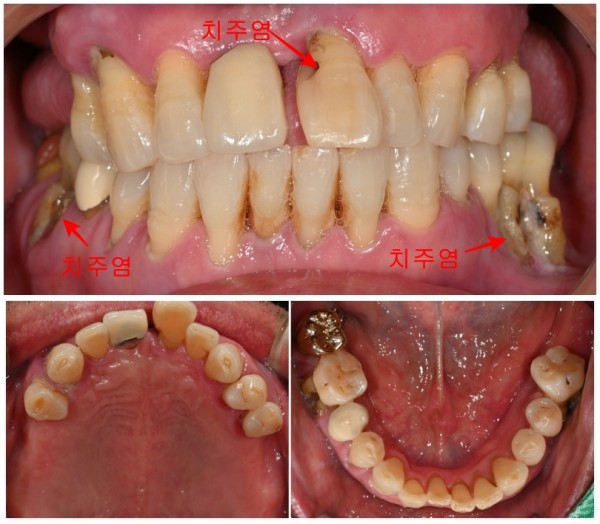

오늘 소개해드릴 사례도 그런 경우 중 하나입니다.

환자분께서는 여러 치아의 심한 흔들림과 불편함으로 내원해주셨습니다.

상담을 진행하면서 알게 된 것은,

몇 년 전부터 증상이 있었지만 바쁜 일정으로 인해

치과 내원을 계속 미루셨다는 점이었습니다.

그러는 사이 불편함은 점점 심해져서

일상생활에 상당한 지장을 받게 되신 상황이었습니다.

앞니 부분과 어금니 부분의 여러 치아에서 치주염이 상당히 진행되어 있었고,